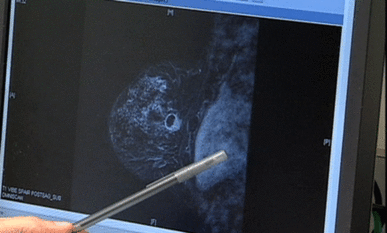

Stress linked to aggressive breast cancer

A new study finds a link between aggressive breast cancer and stress. But the lead researcher suggests the findings raise as many questions as they answer.